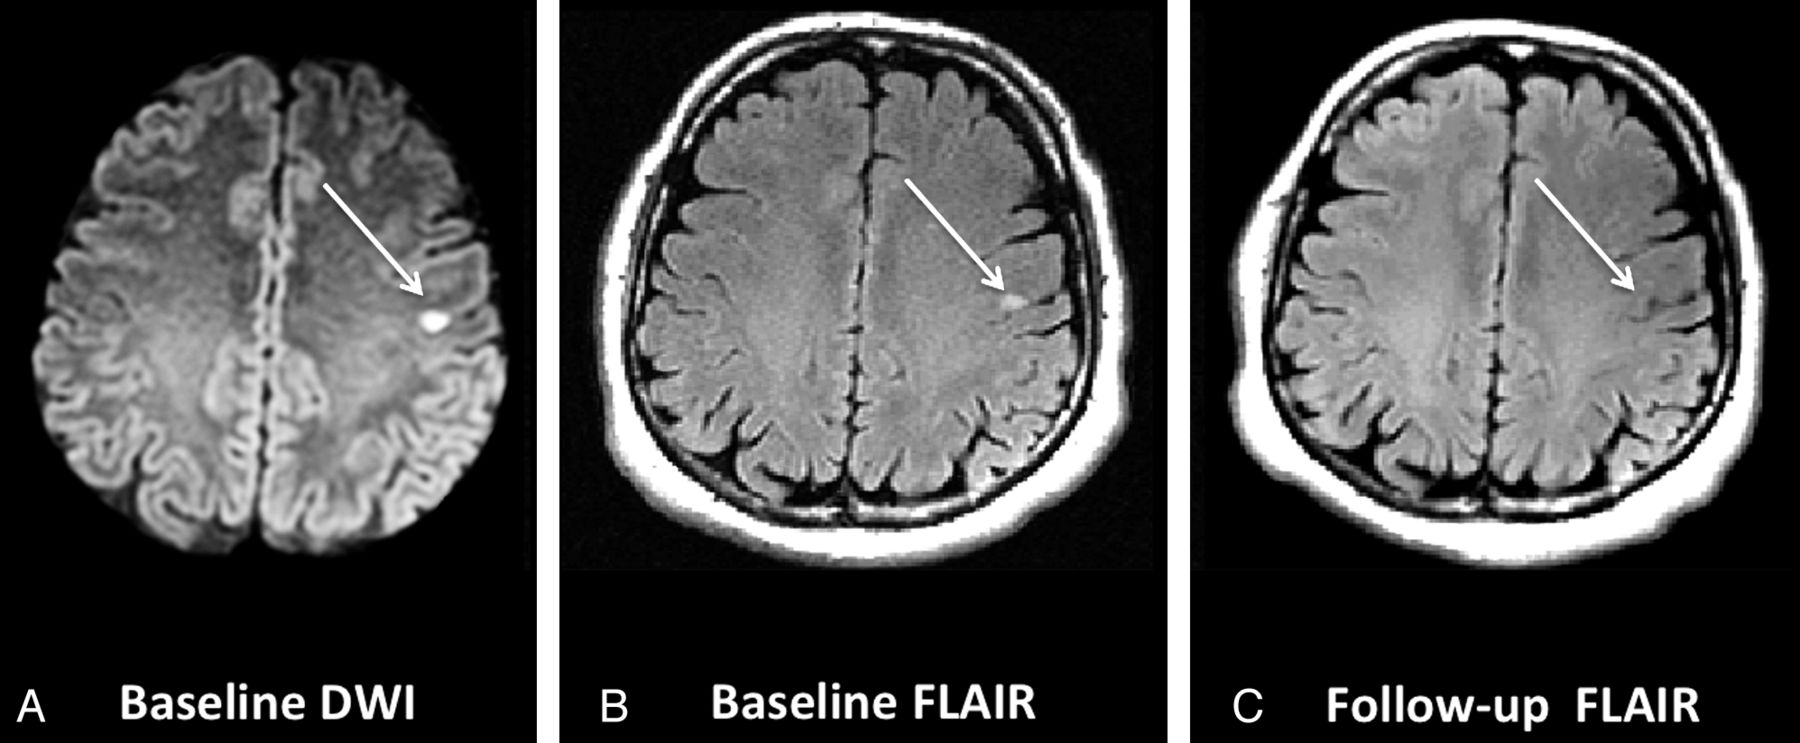

Primary and Secondary Outcome

The primary outcome was the rate of DWI reversal on follow-up FLAIR imaging. This was a priori defined as the absence of T2/FLAIR hyperintense signal on follow-up imaging in the region of the brain with the baseline DWI restriction. The patients were not considered to have DWI reversal if there was evidence of atrophy or gliosis in the same region that had DWI restriction or if they showed partial resolution of signal on follow-up imaging (Fig 1). Secondary outcome was the rate of clinical disability as defined by an mRS score of ≥2 at 90-day clinical follow-up.

Example of focal atrophy on follow-up FLAIR imaging in the region of the original DWI lesion that could mimic DWI reversal. Baseline DWI lesion (A) and baseline FLAIR (B) show the acute ischemic infarct. C, An area of focal atrophy in the region of the baseline DWI lesion.

Example of a patient with DWI reversal. Baseline DWI (A) and baseline FLAIR (B) show the acute ischemic infarct corresponding to the patient's presenting symptoms. C, Complete resolution of the DWI signal on follow-up MR imaging (FLAIR).